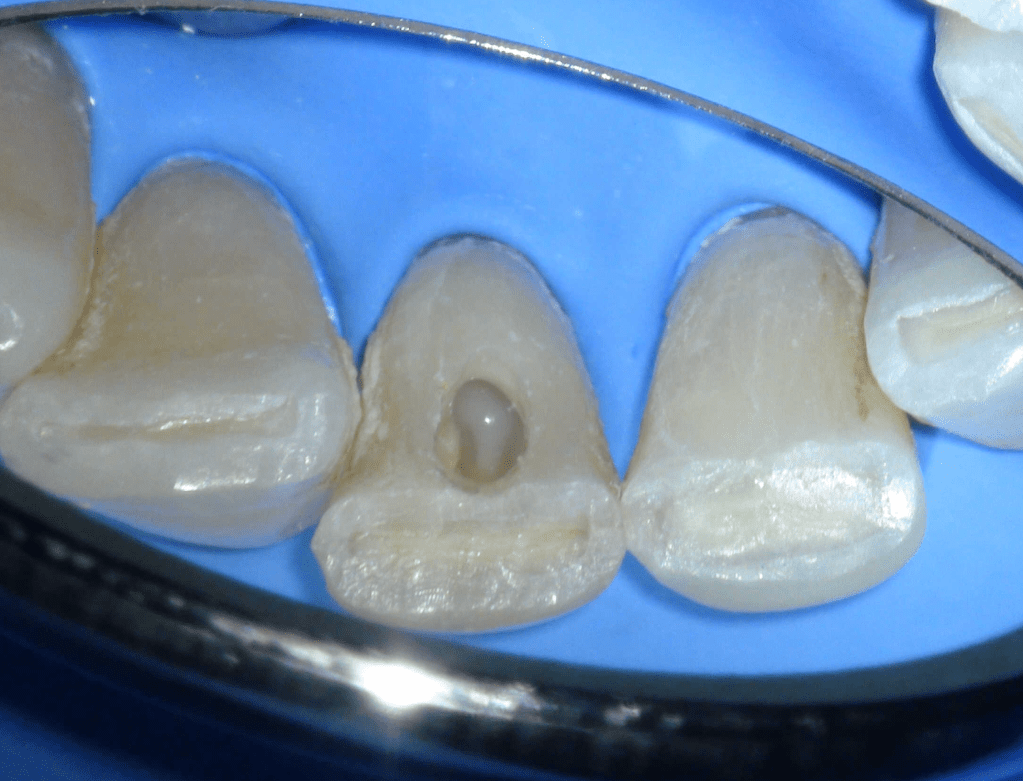

Fistula, dent in dente